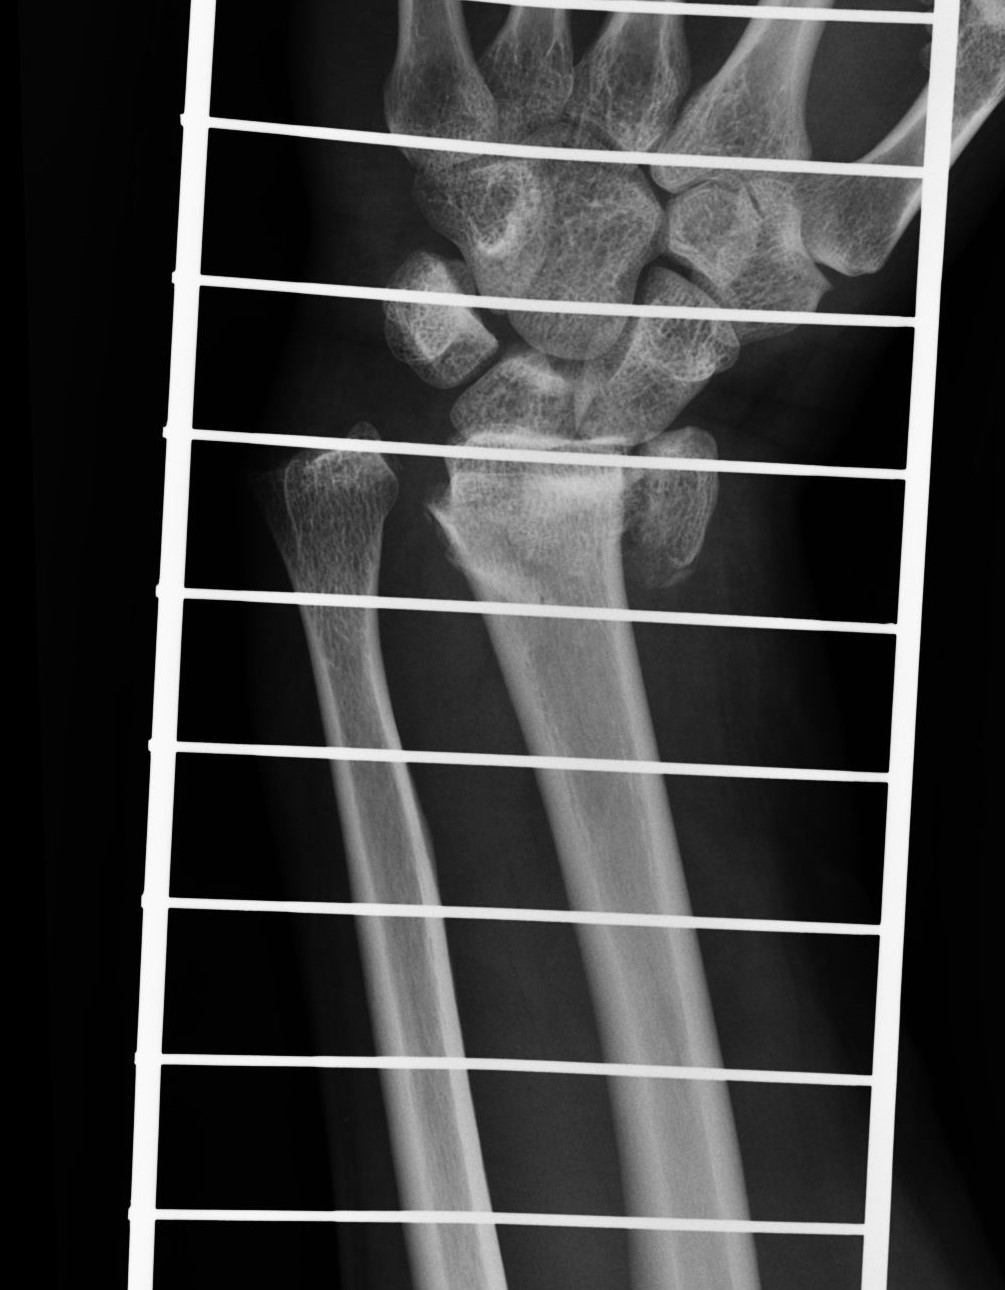

Successful surgery to reduce and fixate with the plate of neglected, displaced fracture of the distal radius

Treatment of neglected, displaced or united distal radial fractures (DRFs) is difficult, because it requires either wedging the almost consolidated fracture and reduction to the correct position, or cutting the united bone and putting it in the correct position (corrective osteotomy). Both treatments are associated with the risk of failure and complications. The paper presents a case of almost fully united DRF in a man, in whom 5 weeks after the injury, and after unsuccessful primary fixation with K-wires, the bone fragments were surgically wedged, aligned and fixed with a palmar plate. The result of treatment after 2 months was satisfactory. Early surgery allowed for a significant shortening of the recovery period and allowed the patient to return to work.